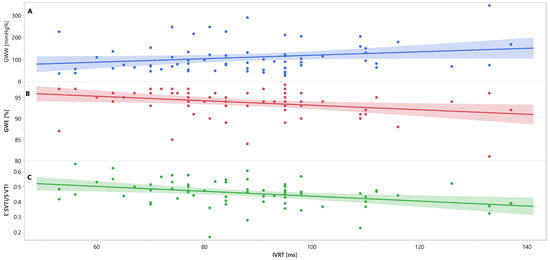

Mutual associations between PSD, GWW, GWE, IVRT and E′VTI/S′VTI are additionally shown in Figure 3, Figure 4 and Figure 5 as linear regressions.

Figure 4.

Linear regression lines for associations between IVRT and GWW (panel A, line and points in blue), GWE (panel B, line and points in red), and E′VTI/S′VTI (panel C, line and points in green) in healthy people. Abbreviations: E′VTI/S′VTI—systolic–diastolic coupling, GWW—global wasted work, GWE—global work efficiency, IVRT—isovolumetric relaxation time.